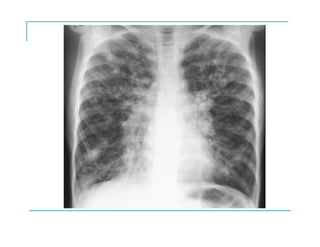

EVOLUCIÓN RADIOLÓGICA

EVOLUCIÓN FUNCIONAL

EVOLUCIÓN A LARGO PLAZO

Nacimiento Tiempo

Reagudizaciones

El porcentaje de caída del FEV1 predice mortalidad

Una caída lenta del FEV1 mejoraría la sobrevida

Konstan MW et al. J Cystic Fibrosis 2009; 8 [suppl 1] S15-S19.